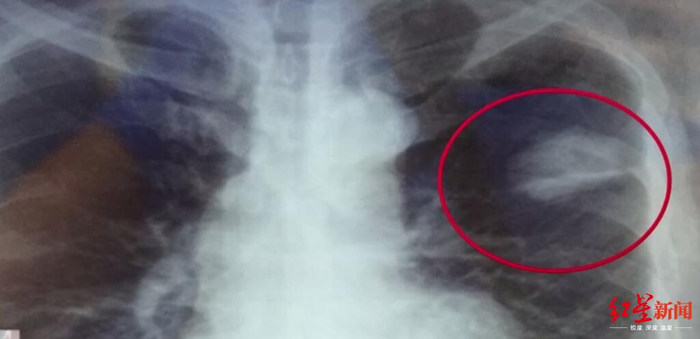

↑体检胸片显示的阴影

离职前,陈志鹏在四川攀枝花的一家健康检查专业机构体检,体检时医生发现其肺部有阴影,认为是其自述的胸前佩戴的玉佩造成的,出具了心肺隔未见明显异常的结论。

在最终出具体检报告前,体检医生再次致电陈志鹏,要求其进行复查,但是他依然提出不用复查。在法庭上,检查陈志鹏胸片的医师出庭,法官对她进行了询问,该女医师称,“就是他(陈志鹏)一直说戴了一个玉佩,正常说来玉佩在胸片上,会显示有阴影的,不可能就消失了,然后再问他症状,他说什么症状都没得,也不咳嗽,也不胸闷,他说正常的很,然后我们结合这些症状和胸片的情况,就出具了未见明显异常的报告。”